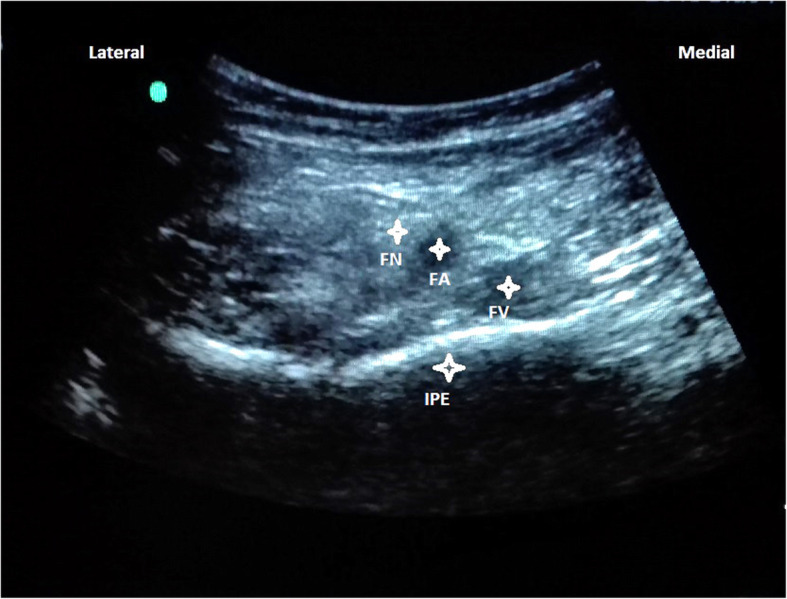

With the patients in supine position, a convex low-frequency (2–5 MHz) ultrasound probe was placed on a transverse plane over the AIIS and then it was aligned with the pubic ramus by rotating the probe counterclockwise at approximately 45 degrees. On this ultrasonographic view, the IPE, femoral nerve and vessels were clearly observed (Fig. 3). So with in-plane approach a 20-gauge and 100-mm needle was inserted from lateral to medial to place the tip in the musculofascial plane between the pubic ramus posteriorly and the psoas tendon anteriorly. Following negative resistence and aspiration tests, the local anesthetic solution composed of a mixture of mepivacaine 1% and ropivacaine 0,5% was slowly injected while observing for adequate fluid spread for a total volume of 20 mL (Fig. 4).

Fig. 3.

Femoral nerve (FN), artery (FA), vein (FV), Iliopubic eminence (IPE)